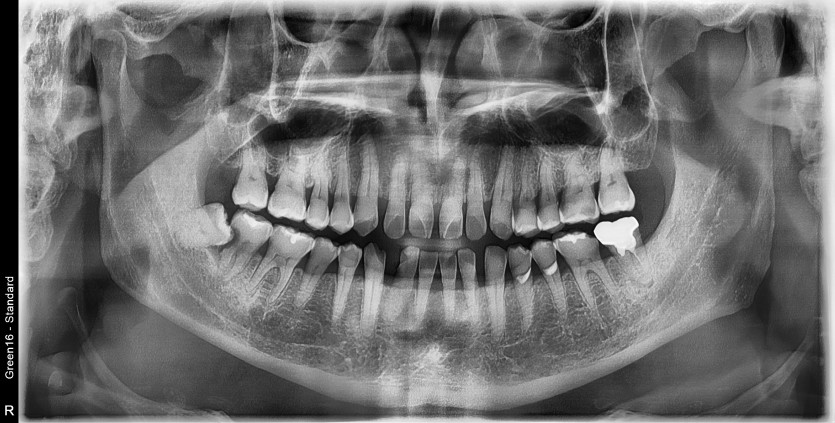

#48 사랑니 발치

구강 외과 전문의가 당일 발치했습니다.